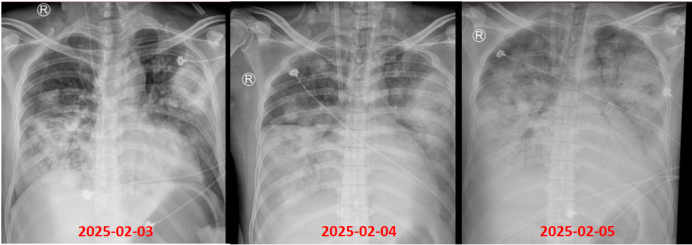

患者为58岁男性,入院检查:WBC 1.59×109/L,LYM 0.11×109/L;病原学提示甲流合并链球菌血流感染。外周血流式细胞术检测单核细胞表面HLA-DR表达率为30%;患者外周血受500 pg/ml内毒素刺激后产生的TNF-α为250 pg/ml;CD4/CD8比值为0.7。治疗1个月后病情好转,顺利出院。患者诊治期间胸部CT变化如图7所示。

图片

7  病例2胸部CT变化情况

从病例1与病例2的临床进程可见,尽管二者基线状态相似,最终转归却存在显著差异,其核心原因在于他们基础免疫状况不同。这一现象凸显了在患者入院初期开展系统性免疫评估的重要性,通过对免疫功能的精准判断,可为后续诊疗策略的制定提供关键依据,进而更好地预测病情走向与干预效果。